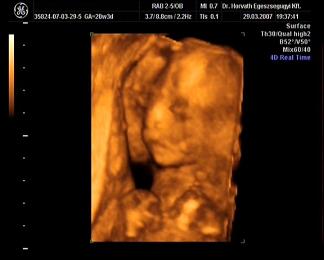

Mi meg megjöttünk az uh-ról, Ákosom nagyon szégyenlősvolt, már ami a kis arcát illeti, mert végig az arca előtt volt mindkétkeze, dörzsölte a szemét....néha profilból el lehetett kapni egy-egy pillanatot, szerintem gyönyörű...már olyan babás! Bezzeg a kukacát, azt mutogatta szorgosan! Meg megmutatta a kezeit, lábait, és hát néha a kis arcát is ki lehetett venni, de szemből teljesen most nem mutatta meg magát. De ami a legfontosabb, minden a legnagyobb rendben Vele, a gerince gyönyörű, gyomortelítődés szépen látható, vesék is szépek, koponya rendben....szóval minden okés, és ez a lényeg. Már 31O gramm a kis Drágám! Nagyon jó volt az egészvizsgálat, csak azt sajnálom, hogy nem sikerült képet készíteni Róla, pedig a doki mindent megtett...deDVD-t kaptunk, majd abból megpróbálok valamit kiügyeskedtetni Apával.

Elsőnek egy profil Kép

porsika